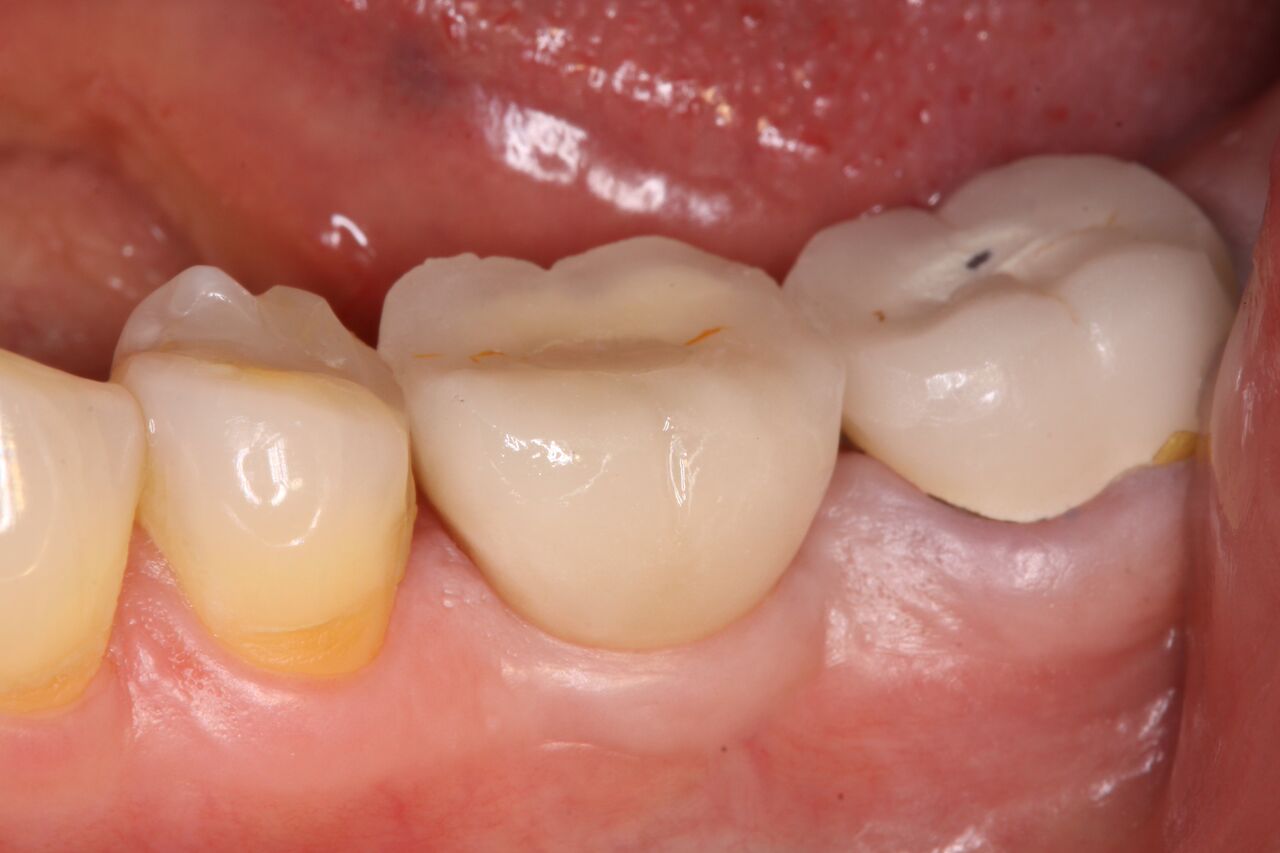

(5.) Immediate restoration of No. 19 day of surgery in infraocclusion.

Figure 5

A 63-year-old woman presented with severe pain on biting of tooth No. 19 (Figure 1). Clinically there was pain on percussion and significant periodontal probing along the mesial root. The patient was anesthetized with infiltration anesthesia and the crown was horizontally sectioned from the lingual of the tooth. The remaining tooth was sectioned so the roots could be extracted individually. The socket was fully debrided and an implant was placed (Figure 2), which was prosthetically correct and stabilized in excess of 45 Ncm. The bone was milled to allow for unimpeded placement of a temporization abutment. The initial crown was revised to be the temporary crown in infraocclusion. Cement was extruded extraorally (Figure 3) prior to seating of the temporary restoration. The socket was sealed with the temporary crown and there were no sutures or bone graft (Figure 4 and Figure 5).